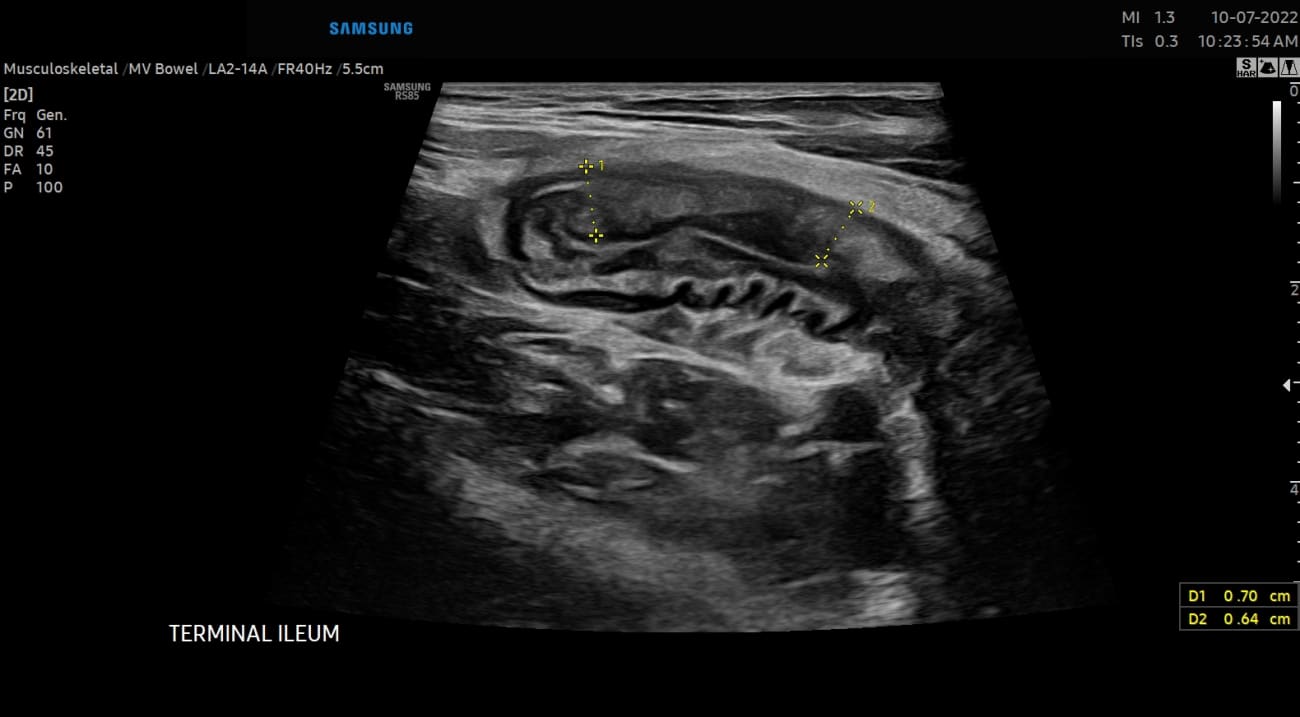

Mount Sinai Brings Patient-Centric Intestinal Ultrasound to North America

Mount Sinai is the first adult and pediatric inflammatory bowel disease center in the United States certified to use intestinal ultrasound for patient care and research. It is now launching efforts to train specialists in the technique.